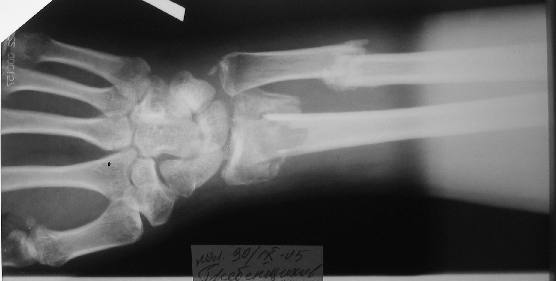

перелом Н/3 предплечья

Больному 27 лет. Травма 2 месяца назад, проводилась закрытая репозиция. Контрольные снимки 3 недели назад (смотреть вложение).

Планируем провести открытую репозицию фиксацию пластинами.

Обдумываем, как провести репозицию? Предварительно провести дистракцию аппаратом внешней фиксации за нескольких дней до открытой репозиции или во время открытой репозиции?

Первоначальное впечатление: если край проксимального отломка лучевой кости не давит на срединный нерв и не нарушает скольжение сгибателей, то достаточно быстро пациент сможет вернуться к труду при продолжении консервативного лечения. Укорочение на 15 мм для неопорного (да и для опорного тоже) сегмента некритично. Имеющиеся осевые смещения вполне компенсируются запасом диапазона фукции суставов. Если край проксимального отломка мешает -- можно резецировать его, не разрушая сфорировавшегося к сегодняшнему дню сращения.